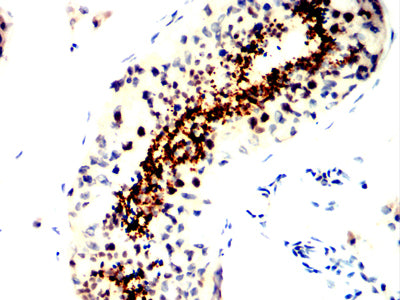

Product Image

IHC | 1/200 - 1/1000 |

SPATA19 (Spermatogenesis Associated 19) is a Protein Coding gene. Diseases associated with SPATA19 include Multiple Mucosal Neuroma. |

Immunogen | Purified recombinant fragment of human SPATA19 (AA: 25-167) expressed in E. Coli. |